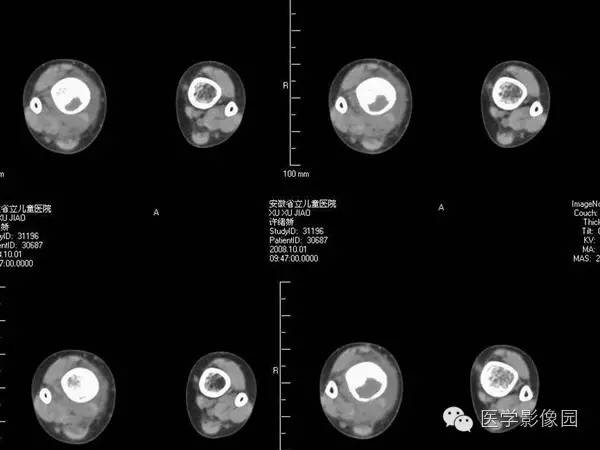

【病例】浆细胞性骨髓炎1例X线及CT影像表现